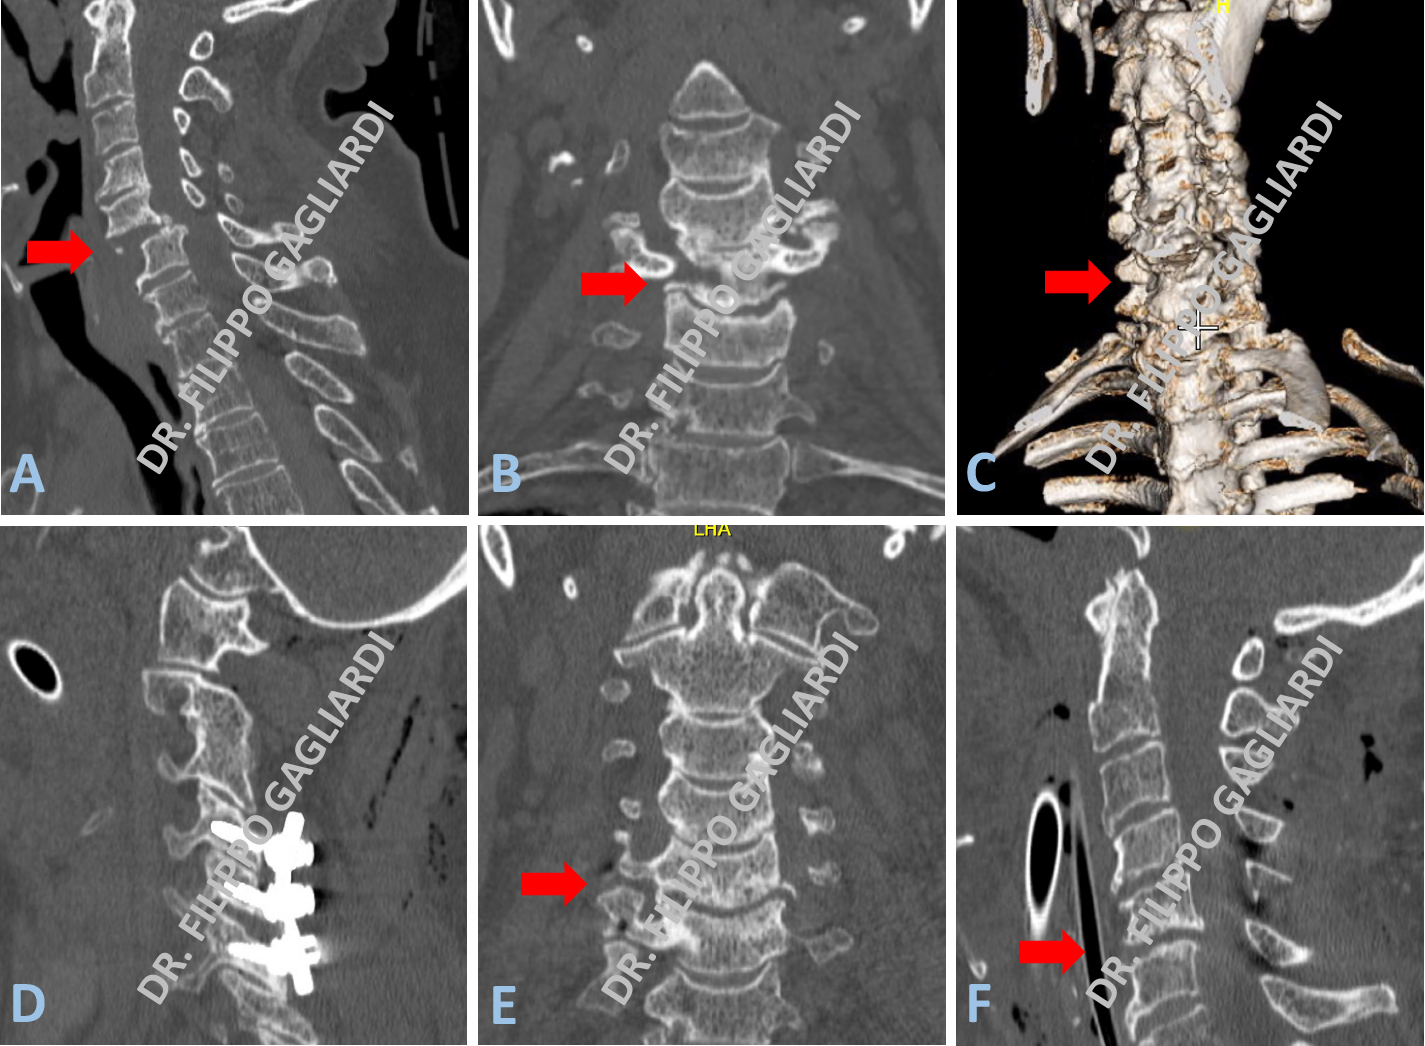

Caso di frattura della quinta vertebra cervicale (C5) con lussazione secondaria della quinta sulla sesta (C6) vertebra cervicale (frecce rosse Figure A, B, C). Il Paziente è stato sottoposto alla riduzione chirurgica della lussazione sotto guida radioscopica (frecce rosse Figure D, E) e a successiva stabilizzazione vertebrale con approccio posteriore dalla quarta (C4) alla sesta (C6) vertebra cervicale mediante viti trans-articolari e barre laterali in titanio. Le Figure A e B mostrano rispettivamente la proiezione sagittale (o laterale) e coronale (o antero-posteriore) della colonna vertebrale all’esame TC pre-operatorio. La Figura C illustra la ricostruzione tridimensionale dell’anatomia pre-operatoria. Le Figura D mostra la proiezione sagittale della TC post-operatoria in cui si apprezzano le viti in sede. Le Figure E e F mostrano l’esito post-operatorio in proiezione coronale e sagittale al controllo TC. L’esame documenta il perfetto riallineamento del vertebre cervicali.